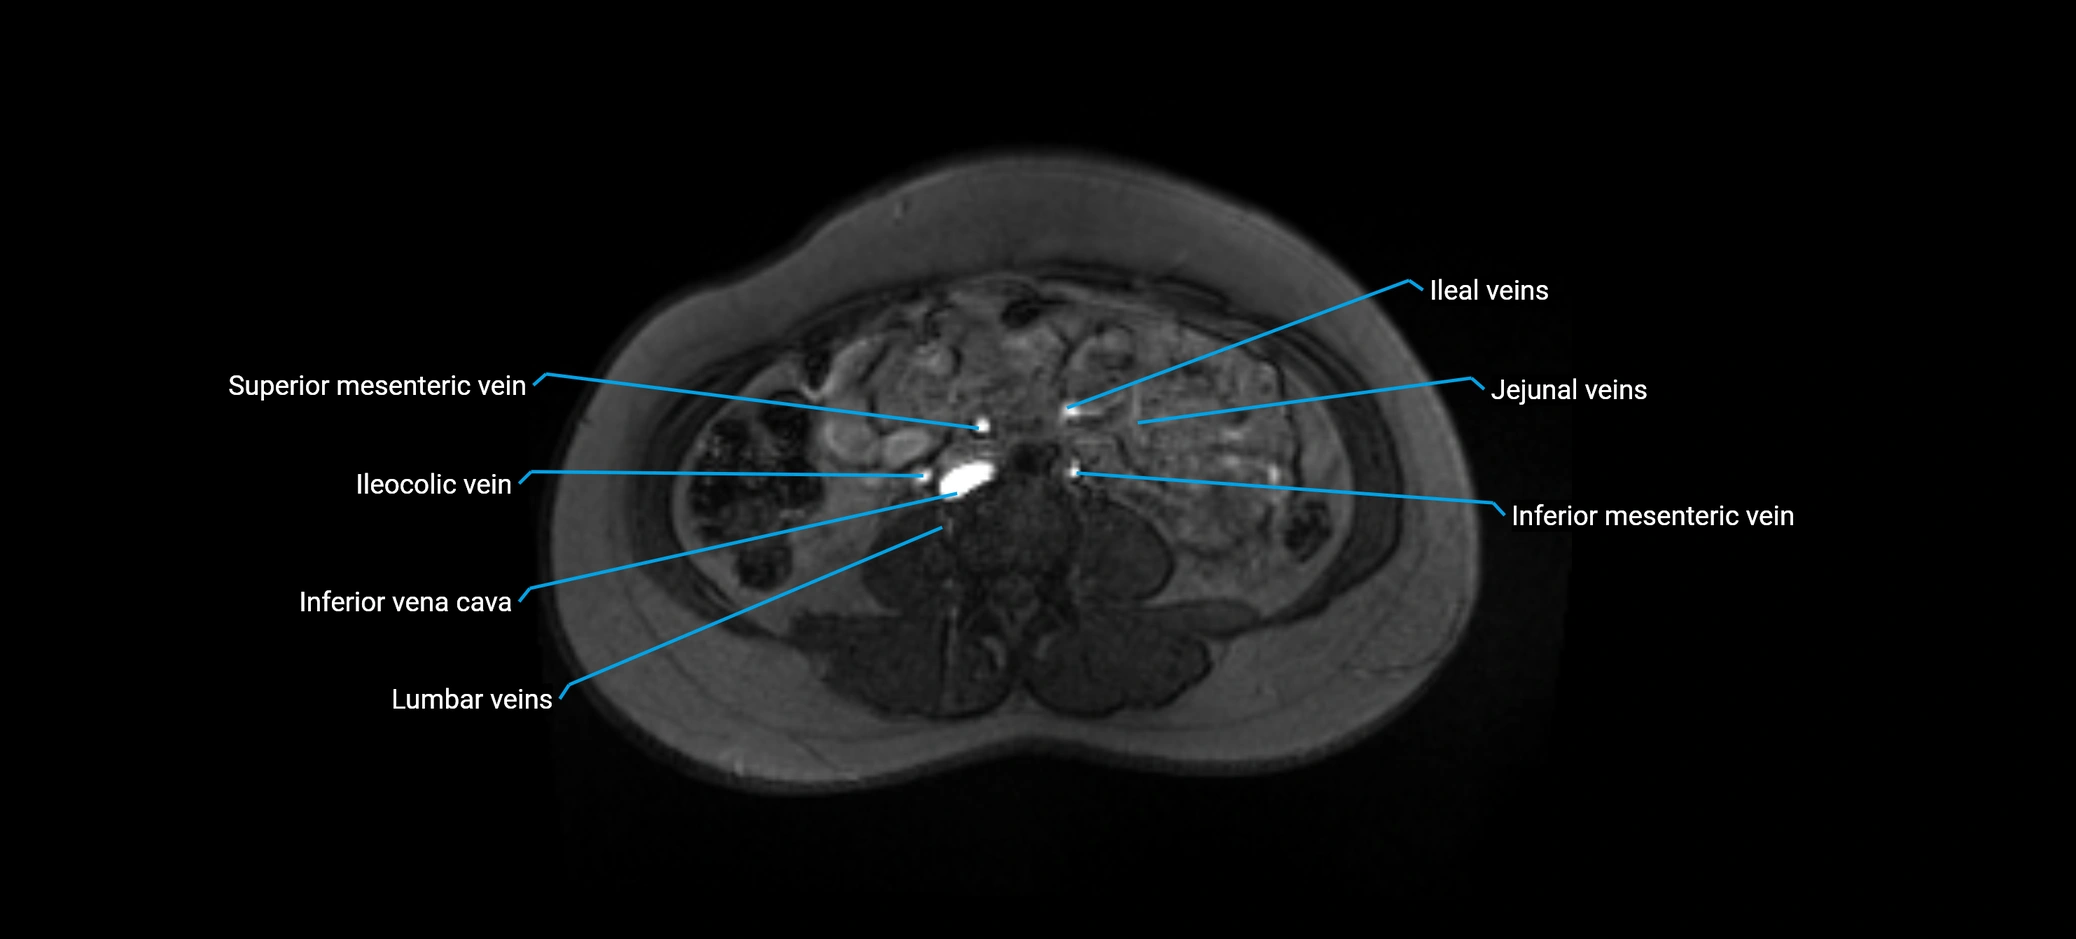

MRI image

image